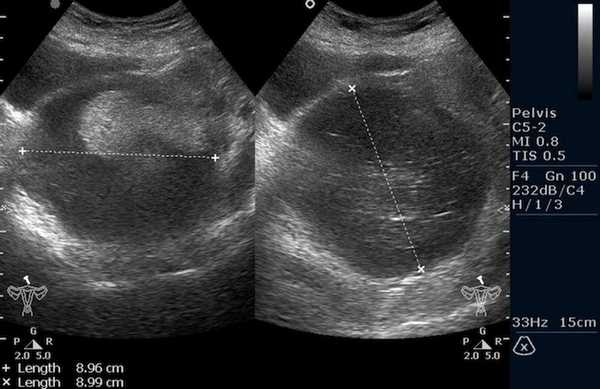

Яичники

Овариальные (расположенные в яичниках, яичниковые) опухоли наиболее часто проявляются болью в животе. При осмотре пальпируется опухоль в малом тазу, часто - в брюшной полости. Также за счет асцита (скопления в брюшной полости жидкости) увеличен живот. Нередко у девочек с таким диагнозом бывает лихорадка.

Самая часто диагностируемая герминогенная опухоль - это дисгерминома. Преимущественно ее обнаруживают во второй декаде жизни. У маленьких девочек встречается редко. Такое заболевания сравнительно быстро распространяется, поражая брюшину и второй яичник. Обычно новообразования односторонние, имеют большие размеры. В связи с этим частое явление - разрыв капсулы новообразования.

Рисунок 3. - тератома яичника а -УЗИ, б — МРТ.

- УЗИ. «Ультразвук» нужен для того, чтобы выявить первичный очаг как гонадной (в половых органах), так и внегонадной герминогенной опухоли. Его также проводят в ходе терапии, чтобы оценить ее эффективность.

![Тератома яичника (УЗИ малого таза)]()

Тератома яичника (УЗИ малого таза)